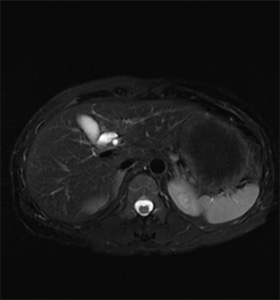

MRI検査室

超伝導磁石が埋め込まれたトンネルに体を入れ磁石と電磁波によって体の中の情報を解析し画像にします。色々な角度から体の断面を画像化することができ、脳、脊髄、臓器、筋肉、関節、血管などの情報を得ることができます。また、X線を使わないため被ばくの心配がありませんが検査中は大きな音がします。